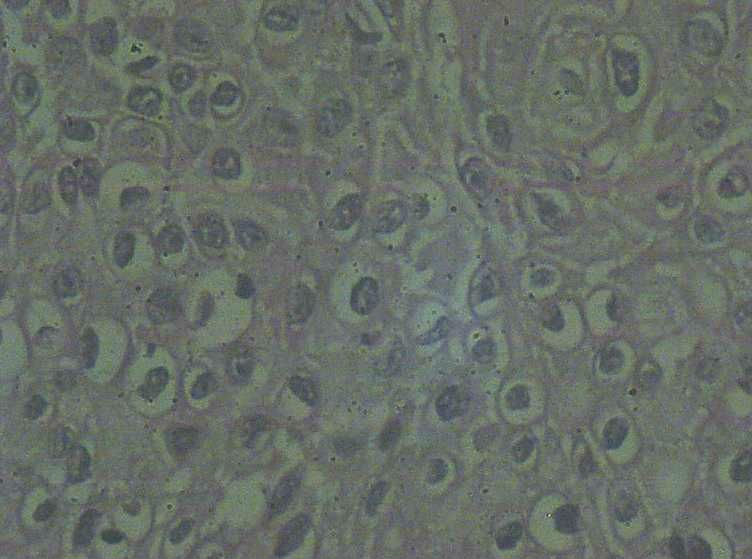

33岁 宫颈刮片看上去很像腺上皮病变,报了AGC 建议活检。 活检取自宫颈,图片如下:请帮忙看下,谢谢!

鳞状上皮增厚,乳头状增生,并见挖空样细胞。提示HPV感染。

有不典型增生, 不知道大家有没有看到。  如果有不典型和上面的图像可或直接报 :尖锐湿疣伴不典型增生。